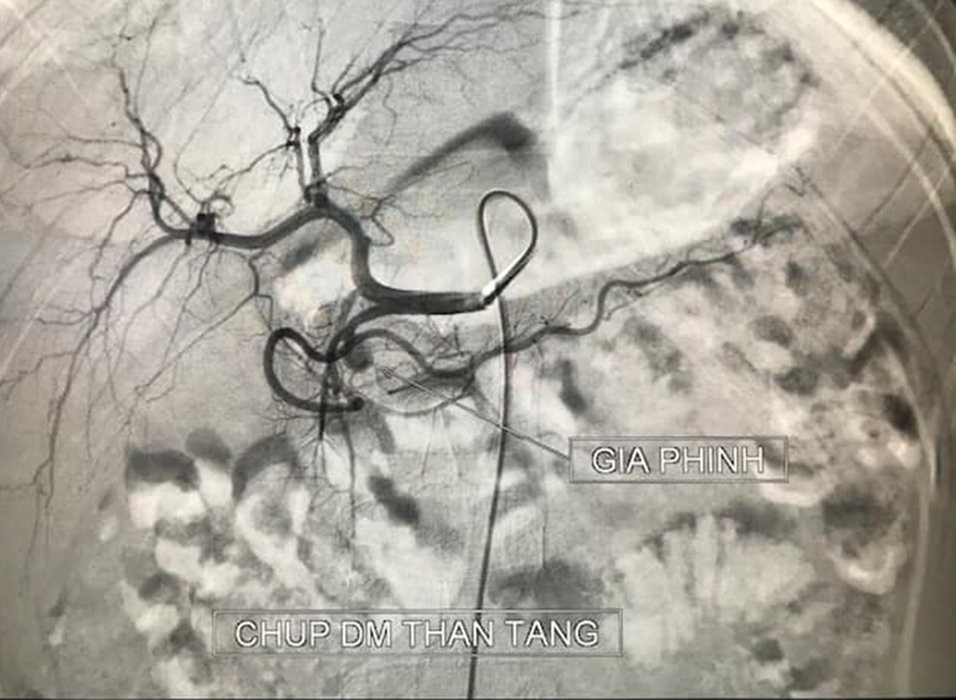

Hình ảnh ổ giả phình lớn động mạch vị tá tràng của bé B. qua phim chụp. (Ảnh: Bệnh viện cung cấp)

TS.BS Lê Thanh Dũng, Phó trưởng khoa Chẩn đoán hình ảnh - Bệnh viện Hữu nghị Việt Đức cho biết: "Phim chụp cắt lớp vi tính cho thấy có ổ giả phình lớn động mạch vị tá tràng của bệnh nhi. Bệnh nhi đang trong tình trạng rất nguy hiểm, có nguy cơ chảy máu ồ ạt, đe dọa tính mạng, nên cần phải can thiệp cấp cứu ngay lập tức.

Sau 20 phút can thiệp, ổ giả phình trong cơ thể cháu bé được loại bỏ hoàn toàn. Bệnh nhi hết nôn ra máu, huyết động ổn định. Hiện tại, bệnh nhân tiếp tục được theo dõi thêm để điều trị tình trạng viêm tụy cấp tại Khoa Nhi, Bệnh viện Hữu nghị Việt Đức".